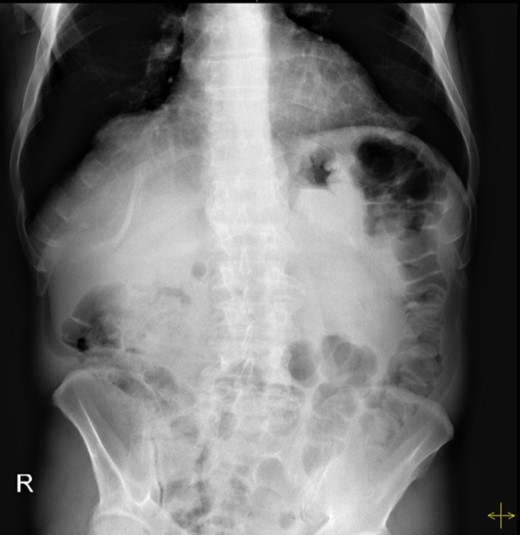

Haematological and biochemical profiling were performed, as well as plain abdominal radiographs (Fig. 4) and abdominal ultrasound, all showing no relevant changes. The upper endoscopy revealed a mild esophagitis. An upper gastrointestinal series was later executed, revealing the presence of an organoaxial volvulus (Fig. 5).

Abdominal radiograph performed during a symptomatic interval, showing no relevant changes.